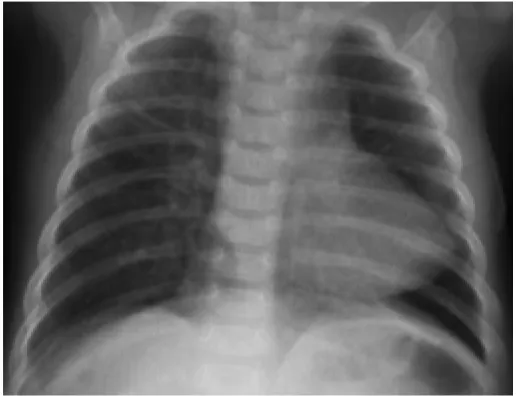

청색증을 동반한 선천성 심장 질환을 가진 4개월된 남자아이가 밤중에 울면서 호흡곤란을 보이며 병원에 도착했다. 산소포화도 측정 결과 65%로 나타났으며, 좌측 흉부에서 미약한 구출성 심잡음이 들렸다. 응급 조치 후 아이의 상태가 호전되어 산소포화도가 85%로 상승하였고, 심잡음이 더욱 뚜렷해졌다. 가슴 X선 검사 결과가 나왔다. 수술을 기다리는 동안 어떤 약물을 투여해야 할까?

• 흉부 X선에서 특징적인 boot-shaped heart가 관찰되며, 좌측 흉골연의 수축기 심잡음이 들리므로 TOF가 의심된다.